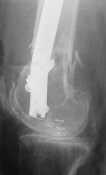

Attached are few examples from our Hospital:

A. Difficult reductions, even in retrograde nailing (my preference, easier control of "small" distal fragment) and it is much, much harder to do it anterograde (Alex, do you have one good case in your collection of anterograde nailing in very distal fractures - as you have suggested that I

should have done it in my previously posted case?

Malpositioning is much too common (recurvatum, varus - valgus).

B. Fixation loosening: distal cutting of the nail, non-unions do happen (cases attached).

Locking Plating has more distal screws than any nail, fixed angles and provides much better fixation, especially in osteoporotic bone.

A new toy is more interesting and fashionable. And anyway it is not panacea, i have already seen presentations with LISS failures like the attached one presented by D.Seligson. And people also demonstrated incisions say that the method is not so LESS invasive as it supposed to be.